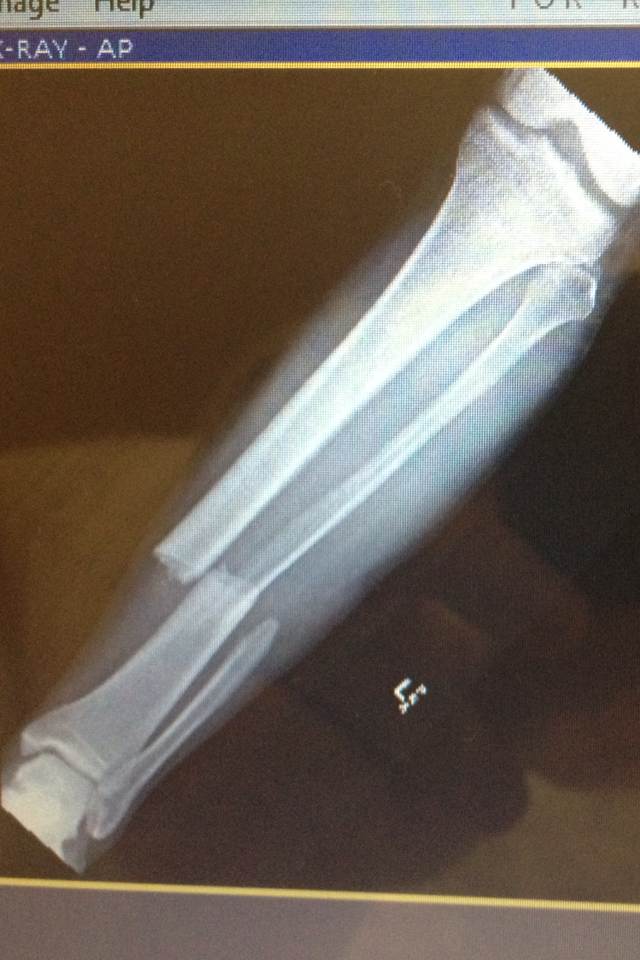

Other ouch..